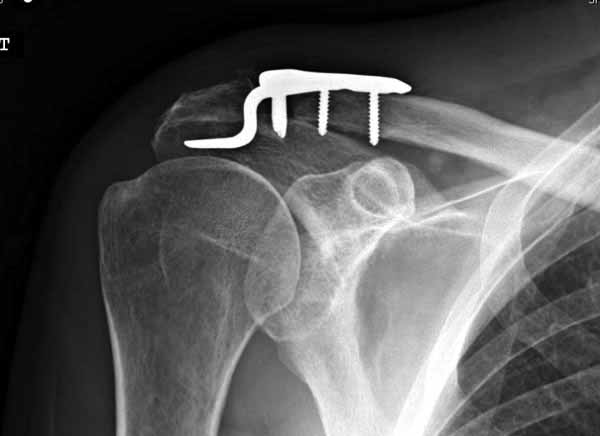

Потом, к сожалению и Юрий, и Вы ошиблись в не существовании такой методики. Открываем AO Principles of Fracture Management\2007\ стр.567-568. Есть еще на сайте АО-травмы Lateral Clavicle≈Dislocations and Fractures≈The LCP Clavicle Hook Plate . Там акцент методики применения ключичной пластинки с крючком именно и при вывихах, и при переломах!!!

Я ставил польскую http://www.chm.pl/pliki/9878cd2387f303265ebad595b2519dce.pdf, но у них еще не опубликована методика

Но это не помешало успешно пациента прооперировать.

Еще раз спасибо Вам и всем форумчанам за внимание к теме и помощь.

1.JPG

60KB (62415 bytes)

Замечание понял, спасибо и нормальные рентгенограммы, молодец!

Вопрос "ключичной пластины с крючком при акромиальных переломах" я буквально понял, что ведется разговор насчет перелома акромиального отростка, т.е. самого акромиона. И поэтому ссылка на Acumed, они делают пластину для акромиона!

Во вторых, это хорошо что нашли длинную пластину, я об этом писал "пластина короткая, не покрывает медиальный диафизарный фрагмент ключицы", и у нас не получилось, пластина не выдержала...